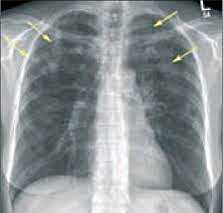

(Слева) На аксиальной КТВР у пациента с простой легочной эозинофилией, выполненной во время обострения заболевания (слева) и месяц спустя (справа), визуализируются разбросанные участки «матового стекла», впоследствии практически полностью разрешившиеся.

(Справа) На аксиальной КТ с КУ у мужчины 42 лет с синдромом идиопатической гиперэозинофилии, с жалобами на нарушение дыхания и эритематозную сыпь по всему телу, с персистирующей эозинофилией на протяжении восьми месяцев, визуализируются неспецифические диффузные участки «матового стекла» в обоих легких.

• ПЛЭ:

о Одно- или двусторонние субсегментарные участки консолидации

о Разбросанные субплевральные очаги ± симптом «гало»

о Разбросанные участки «матового стекла»

о Полости в очагах и плевральный выпот отсутствуют

• СИГ:

о Отек легких, обусловленный сердечной недостаточностью:

- Равномерное утолщение междольковых перегородок, утолщение бронховаскулярных пучков

о Периферические очаги от нескольких миллиметров до сантиметра ± «матовое стекло» на периферии

о Солитарные или множественные участки «матового стекла» с периферическим распределением